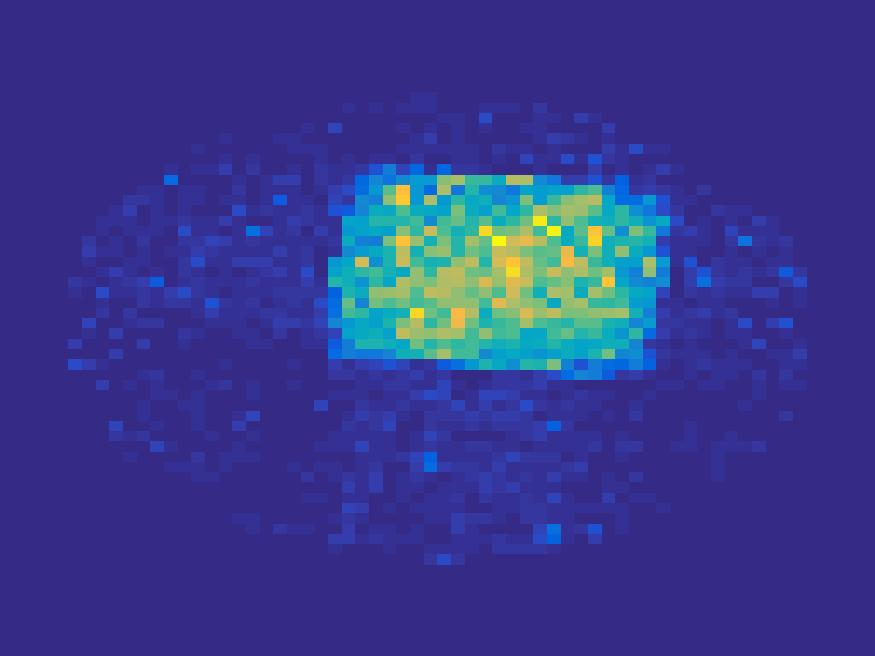

For the simulated images of rat’s abdomen, the same procedure is applied to generate projection data. Also, noise was added to the sinogram. Figure 5 compares the frames reconstructed by different methods. Clearly, the traditional FBP method and least square method cannot reconstruct the dynamic images with very few projections, however the proposed method reconstructs the images quite accurately. Figure 6 illustrates the comparison of the true TACs and those reconstructed by the proposed method. We can see that they are quite accurate and present small errors.

| Frame 1 | Frame 11 | Frame 21 | Frame 31 | Frame 41 | Frame 51 | Frame 61 | Frame 71 | Frame 81 |